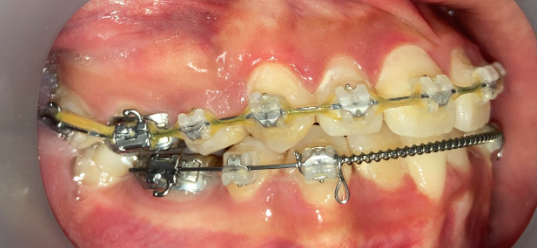

リカバリー症例1

他院の非抜歯矯正後、当院で再治療したケース

リカバリー症例の初診時の口腔内|奈良の矯正歯科

初診時

抜歯矯正1年後の口腔内|奈良の矯正歯科

治療1年後

抜歯矯正完了後の口腔内|奈良の矯正歯科

治療完了

他院で非抜歯矯正を受け、歯並びは改善したものの、口元の突出感が残ったまま治療が終了。当院で精密検査を行った結果、上下4本の抜歯によるリカバリー治療が必要と判断しました。